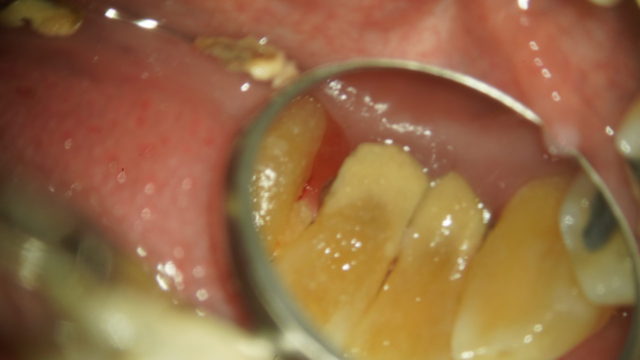

こちらの写真は歯の裏側にびっしりと付いてしまった歯石です。

歯医者で超音波を使用して歯石を取ります。写真右側はまだ歯石が付着していますが左側は歯石を取った後です。